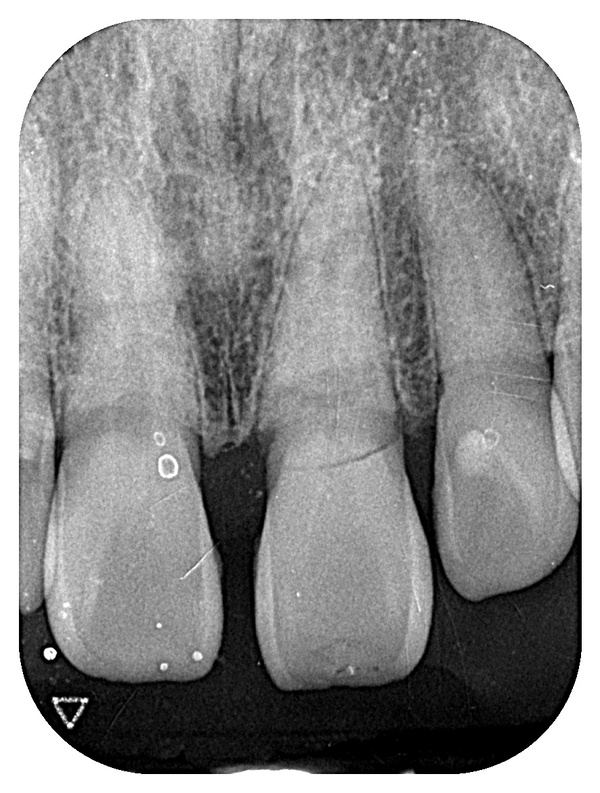

こちらが初診時のレントゲン写真になります。

左上1番目の歯が根元で横に折れてしまっているのが分かるかと思います。